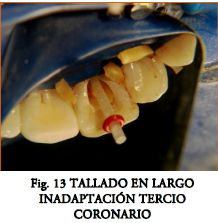

La adaptación a las paredes debe ser proporcional a la palanca extrarradicular (nunca menor a 7 u 8 mm de íntima adaptación poste-pared) y deben utilizarse mecanismos compensatorios (fig.21) en caso de existir zonas de inadaptación. Debe procurarse un calibrado cuidadoso usando fresas no excéntricas, de buen corte y sin realizar movimientos laterales.

La recomendación usual del fabricante de cementar el poste y luego tallar la corona, puede dificultar el correcto posicionamiento en sentido mesio-distal o vestíbulo-lingual. Además impide apreciar el espesor de las paredes debilitadas por el tallado (usualmente la vestibular) (Figs. 14, 15, 16, 17). Por otro lado también complica el cambio de estrategia (habría que fresar el poste ya cementado).

Tallado en Largo.- Se utiliza una fresa “Largo” para conducto. Se respetan como mínimo 4 mm de obturación, buscando hacia apical un sector de adaptación bien calibrado dada la expulsividad del tercio coronario.

- Rebasado del Poste.- Se buscó minimizar el desajuste radicular (Fig. 13), por medio del rebasado anatómico.